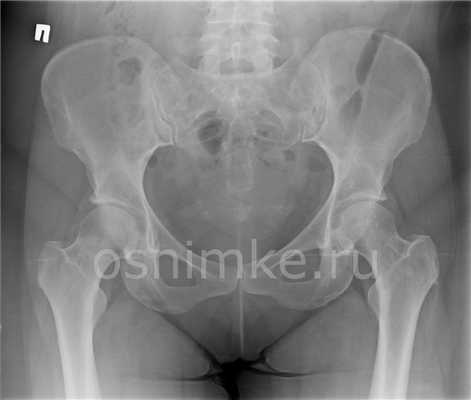

Максимальную визуальную информацию дает рентген тазобедренного сустава в двух проекциях: в прямой проекции (или фронтальной), получаемой фокусировкой рентгеновской трубки перпендикулярно плоскости тела — спереди или сзади, и аксиальной (поперечной или горизонтальной плоскости), фиксирующей элементы сустава сверху вниз — вдоль бедренной кости. Также снимок может делаться при боковой проекции, то есть пациент должен лечь на бок, согнув ногу в коленном и тазобедренном суставах.

При обычной рентгенографии обычно делается переднезадняя и боковая рентгенограмма бедра. Переднезадняя рентгенограмма бедра включает изображения обеих сторон бедра на одной и той же пленке и выступает в направлении середины линии, соединяющей верхнюю часть лобка симфиза и передне-верхнюю подвздошную ость; расстояние между рентгеновской трубкой и пленкой должно составлять 1,2 метра. Если рентгенограммы переднезаднего бедра сделаны в положении лежа на спине, одной из наиболее распространенных ошибок является искажение изображения при повороте бедра снаружи.

Таким образом, либо обе коленные чашечки должны быть направлены вперед, либо нижние конечности должны быть повернуты внутрь на 15-20 ° для приспособления бедренной антиверсии на рентгенограммах переднезаднего бедра.

Каждая рентгенограмма дает важную информацию, необходимую для точной диагностики заболеваний тазобедренного сустава . Как правило, переднезадний профиль предоставляют информацию о форме вертлужной впадины, тогда как другие боковые изображения предоставляют информацию о проксимальных отделах бедра, включая головку бедра.

На рентгенограммах переднезаднего бедра может быть получена следующая информация:

- длина ноги,

- угол шейки,

- покрытие вертлужной впадины: угол наклона латерального центрального края (СЕ) и индекс выдавливания головки бедра,

- глубина вертлужной впадины,

- наклон вертлужной впадины,

- версия вертлужной впадины,

- сферичность головы и

- ширина суставного пространства.

На боковых рентгенограммах тазобедренных суставов оценивается форма и смещение сочленения головки бедра и бедреной кости, а также смещение угла альфа.